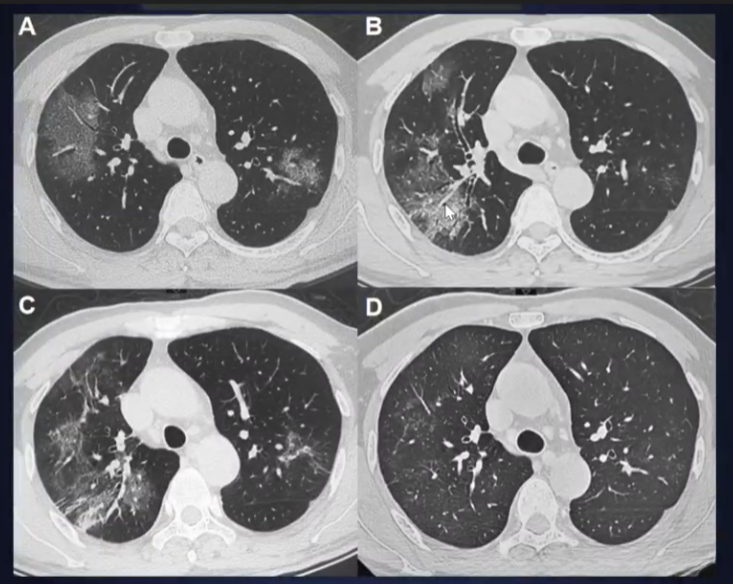

基于CT表现的病变分期

- 早期:病变局限;胸膜下/支气管血管束分布;结节斑片状GGO,其内血管影、间隔增厚

- 进展:病灶增多,范围扩大;铺路石征明显,磨玻璃影与时变共存;局部结构扭曲,支气管扩张

- 重症:双肺弥漫性浸润,实变+磨玻璃影,少量胸水等

CT患者某一加重过程